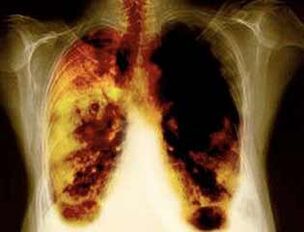

- Samazinot plaušu vēža attīstības risku un daudzus citus vēža veidus.

- Samazinot noteiktu plaušu slimību attīstības risku (piemēram, hroniskas obstruktīvas plaušu slimības).

- Laika posmā no 2 nedēļām līdz 3 mēnešiem pēc smēķēšanas noraidīšanas plaušu darbs uzlabojas un jūtams spēka pieaugums.

- Pēc 1-9 mēnešiem notiek klepus un elpas trūkums: cilijas (sīki mati) sāk normāli ārstēt gļotas, attīrot plaušas un samazinot infekcijas risku.

- 10 gadus pēc smēķēšanas pārtraukšanas par 40%plaušu vēža varbūtība samazinās par 40%.